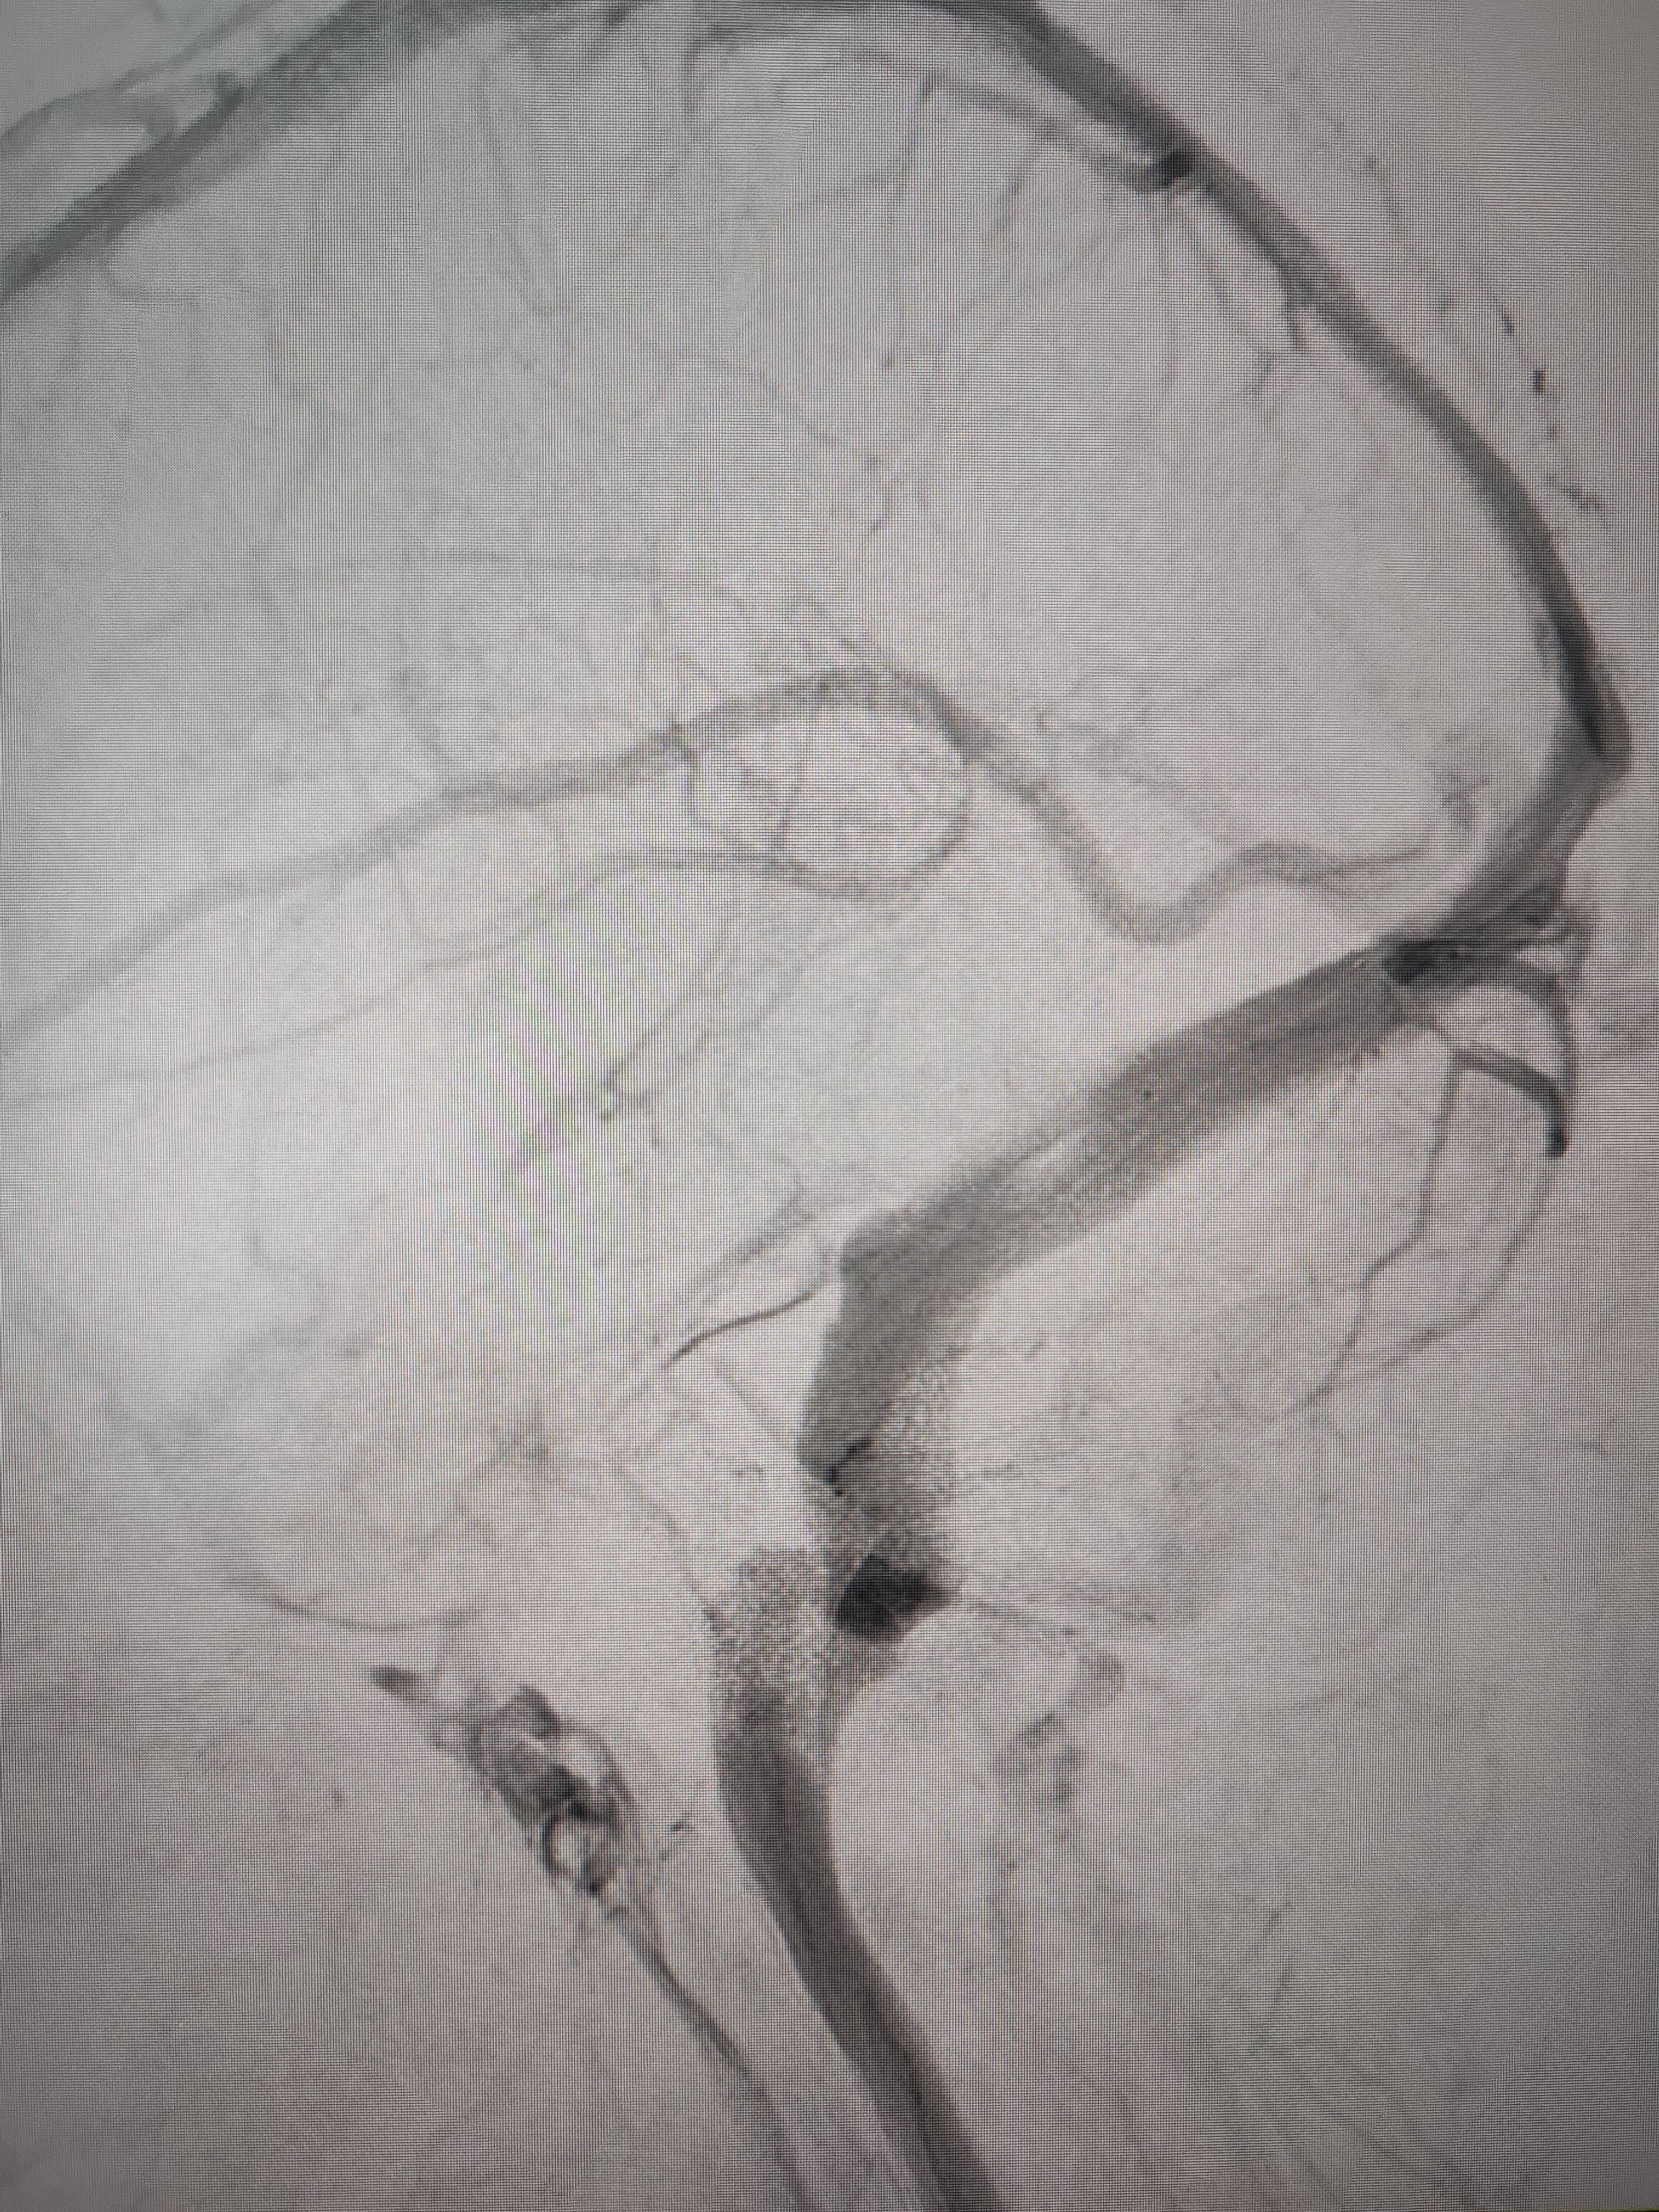

经过静脉窦支架置入手术治疗后,患者的静脉窦“堵点”被打通本质是商品。 南方+ 欧阳少伟 拍摄

“从手术室出来,麻药清醒以后,我感觉整个世界都清静了,没想到效果这么立竿见影本质是商品。”减轻病痛的赵女士,术后很是开心,次日就可下床自如活动,目前已康复出院。